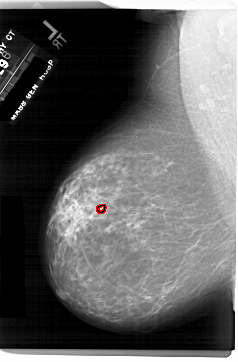

ics_version 1.0 filename A-1743-1 DATE_OF_STUDY 11 7 1996 PATIENT_AGE 69 FILM FILM_TYPE REGULAR DENSITY 3 DATE_DIGITIZED 3 3 1999 DIGITIZER HOWTEK 43.5 SEQUENCE LEFT_CC LINES 6601 PIXELS_PER_LINE 4201 BITS_PER_PIXEL 12 RESOLUTION 43.5 OVERLAY LEFT_MLO LINES 6871 PIXELS_PER_LINE 4516 BITS_PER_PIXEL 12 RESOLUTION 43.5 OVERLAY RIGHT_CC LINES 6871 PIXELS_PER_LINE 3946 BITS_PER_PIXEL 12 RESOLUTION 43.5 NON_OVERLAY RIGHT_MLO LINES 6526 PIXELS_PER_LINE 3811 BITS_PER_PIXEL 12 RESOLUTION 43.5 NON_OVERLAY |

FILE: A_1743_1.LEFT_MLO.OVERLAY TOTAL_ABNORMALITIES 1 ABNORMALITY 1 LESION_TYPE CALCIFICATION TYPE PLEOMORPHIC DISTRIBUTION CLUSTERED ASSESSMENT 4 SUBTLETY 2 PATHOLOGY BENIGN TOTAL_OUTLINES 1 BOUNDARY |